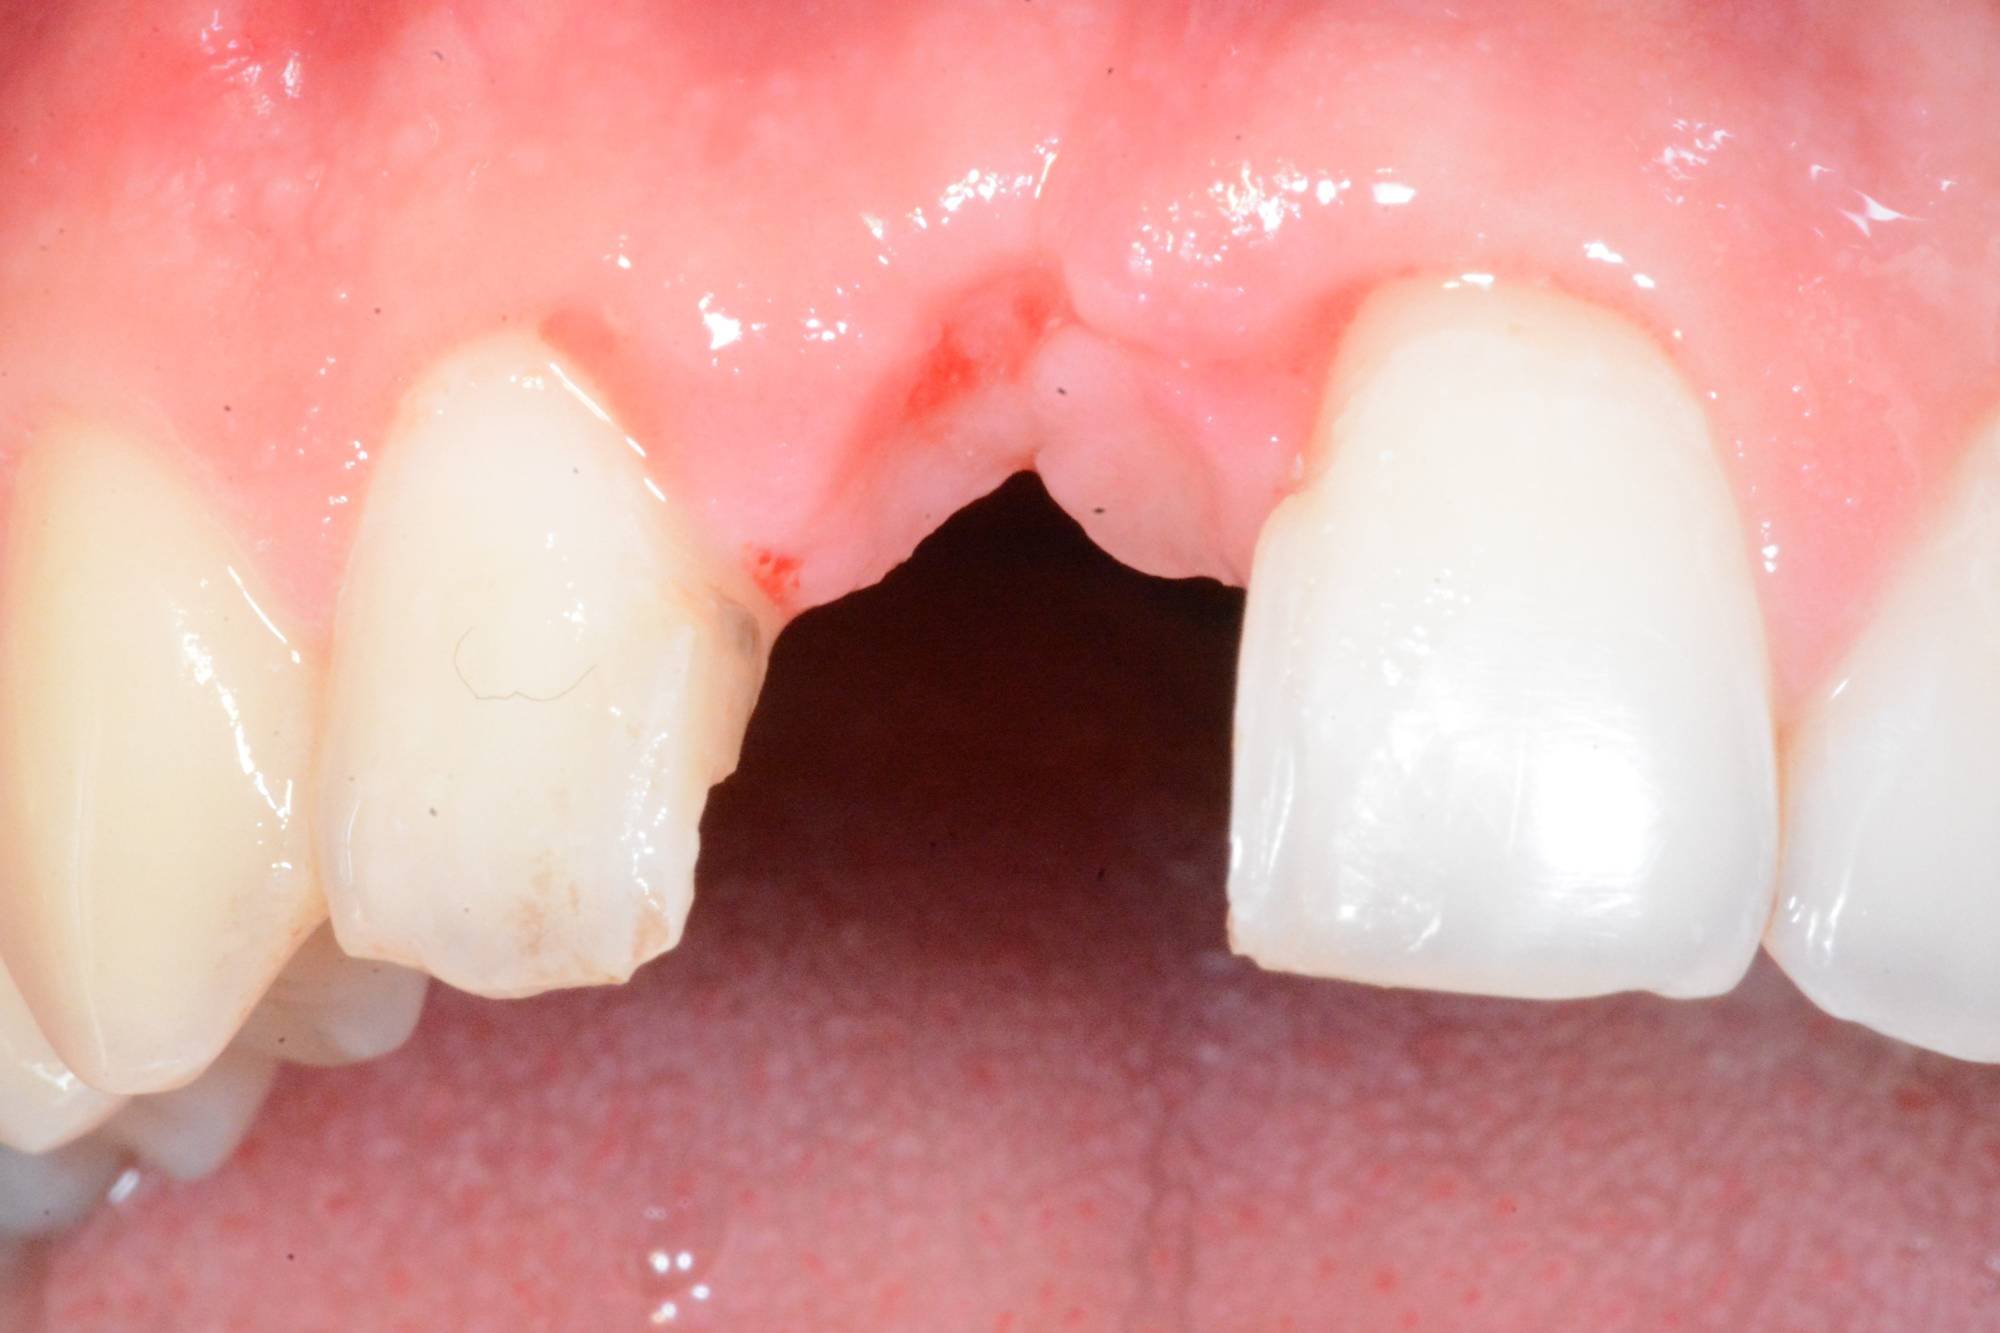

Indovina dov'è l'impianto, memory game

Ti sembra tutto normale in questa foto? Incisivi allineati e con un bel colore chiaro, gengive perfette e assolutamente non infiammate. E se invece ti dicessi che uno di questi denti è un impianto? Su quale scommetteresti? Ti sei mai fatto dei problemi a scoprire i denti quando ridi? Alle volte una caduta accidentale o un trauma durante un’attività sportiva possono toglierti la voglia di ridere liberamente. Guarda la foto successiva e capirai. A questo punto cosa potrebbe capitare? Inizi a sorridere con le labbra sigillate perché ti vergogni del tuo “buco” mentre ridi e ti diverti in compagnia. Questo giovane ragazzo ha perso l’incisivo centrale durante una partita di calcio fra amici. Aveva addirittura perso la parte esterna dell’osso che lo teneva in posizione. Ho dovuto mettergli un impianto osteointegrato e fare quello che noi dentisti chiamiamo “rigenerazione ossea guidata” per ricostruirgli l’estetica naturale che vedi nella prima foto. Solo nella terza puoi vedere cosa c’è dentro, al posto del suo dente ormai perso. La cosa bella è che non è mai stato senza il suo dente, nemmeno per un giorno. Premesso che è sempre meglio curare e salvare i propri denti, quando li devo sostituire, puoi contare sull’efficacia e sull’aspetto naturale degli impianti dentali. Questo ed altro è quello che facciamo nello Studio dentistico del dott. Fabio Ballestrasse a Besana Brianza (MB) e se sei di Verano Brianza, puoi raggiungerci facilmente.